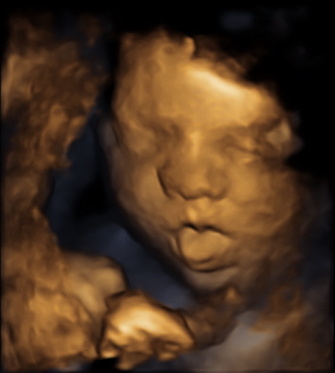

Snímek jasně demonstruje, že v prostoru vymezeném plodovými obaly začíná být plodu poněkud těsno. V blízkosti obličeje jsou zachyceny jak horní, tak dolní končetina. Na chodidle nožičky (dolní šipka) je dobře patrný mohutnější paleček (horní šipka) a štíhlejší prsty. Autorem UZ snímku je MUDr. Radan Doubek, autor popisu MUDr. Šťastná.

Autor UZ snímků je MUDr. Romana Gerychová.